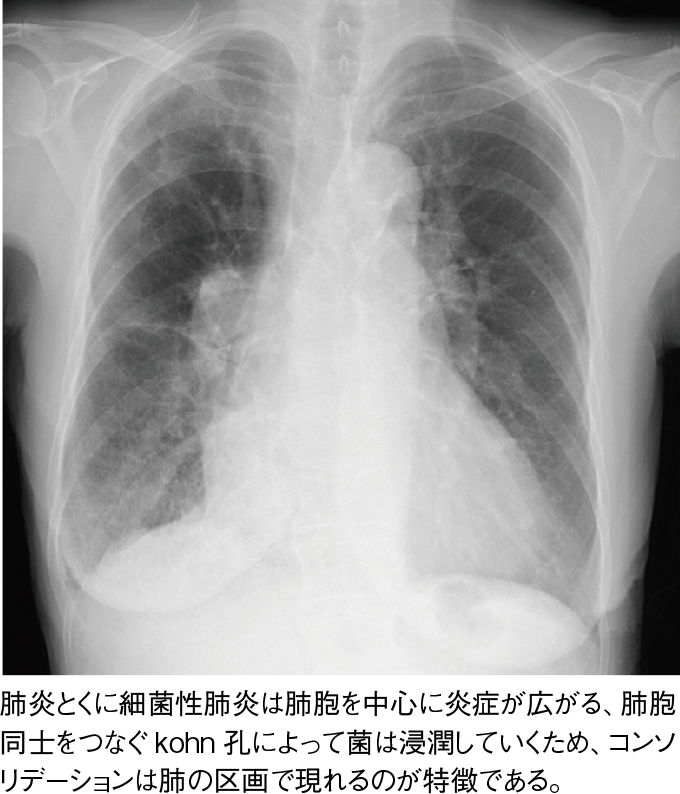

コンソリデーション:

浸潤影ともよばれる。特に細菌性肺炎など肺胞内に滲出液が満たされるような疾患で多くみられる。これは滲出液が肺胞にたまり肺胞全体が水に近い濃度となるため、白く映るためである。無気肺と異なる点は、無気肺は肺胞がつぶれ容量が減少するのに対して、肺炎は肺胞それ自体の構造は変わらない点である。そのため、容量は減少しない。

写真5肺炎:右下葉優位の細菌性肺炎